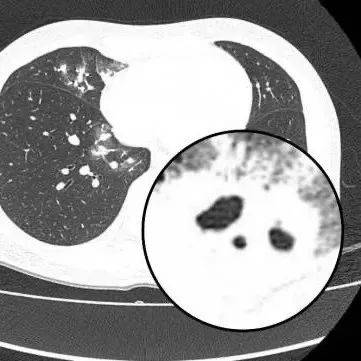

医生查房时,捕捉到CT上形似“鬼脸”的非凡影象(即“鬼脸征”),并伴随“晕伦征”,高度怀疑隐球菌肺炎。医生追问夏女士近期是否曾接触鸟类、禽类及豢养宠物,夏女士否认。

在影象学表现方面,典范CT表现是单发/多发结节伴“晕轮征”,结节液化坏死可形成空洞形似“鬼脸征”,空洞常为薄壁空洞、无液平。